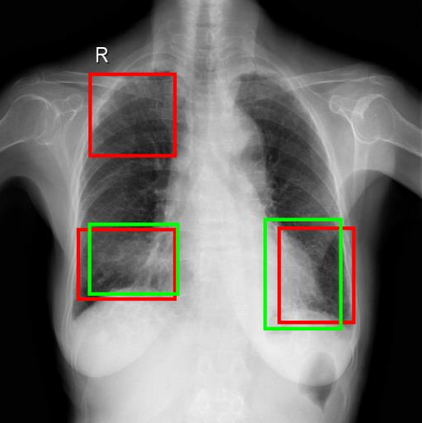

Chest X-ray (CXR) is the most typical diagnostic X-ray examination for screening various thoracic diseases. Automatically localizing lesions from CXR is promising for alleviating radiologists' reading burden. However, CXR datasets are often with massive image-level annotations and scarce lesion-level annotations, and more often, without annotations. Thus far, unifying different supervision granularities to develop thoracic disease detection algorithms has not been comprehensively addressed. In this paper, we present OXnet, the first deep omni-supervised thoracic disease detection network to our best knowledge that uses as much available supervision as possible for CXR diagnosis. We first introduce supervised learning via a one-stage detection model. Then, we inject a global classification head to the detection model and propose dual attention alignment to guide the global gradient to the local detection branch, which enables learning lesion detection from image-level annotations. We also impose intra-class compactness and inter-class separability with global prototype alignment to further enhance the global information learning. Moreover, we leverage a soft focal loss to distill the soft pseudo-labels of unlabeled data generated by a teacher model. Extensive experiments on a large-scale chest X-ray dataset show the proposed OXnet outperforms competitive methods with significant margins. Further, we investigate omni-supervision under various annotation granularities and corroborate OXnet is a promising choice to mitigate the plight of annotation shortage for medical image diagnosis.